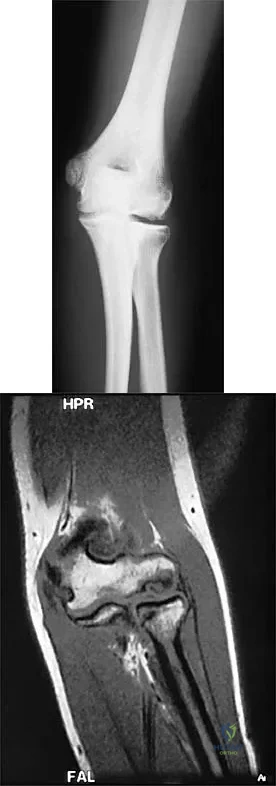

Figures 29a and 29b show the radiographs of a 13-year-old competitive gymnast who has had elbow pain for the past 2 weeks. The pain is worse with tumbling activities. Examination reveals a mild effusion and slight limitation of extension and forearm rotation with no locking. Initial management should consist of

Explanation

The radiographs show a lesion in the capitellum that is consistent with osteochondritis dissecans. There is no evidence of a loose body at this time. Initial management should consist of cessation of gymnastic activities. Nonsteroidal anti-inflammatory drugs and ice may help to alleviate acute symptoms; most symptoms usually resolve in 6 to 12 weeks. The patient may then begin range-of-motion and strengthening exercises, with a slow return to activities once full range of motion and good strength have been achieved. However, the prognosis for a return to high-level competitive gymnastics is guarded. Surgery is indicated for intra-articular loose bodies, a locked elbow, or failure of nonsurgical management. Surgery may be done either open or arthroscopically. Loose bodies should be removed, and cartilage flaps should be debrided. The results of bone grafting and internal fixation generally have been poor. Drilling the base of the defect may stimulate replacement with fibrocartilage, but the benefits of this procedure are not well documented. Maffulli N, Chan D, Aldridge MJ: Derangement of the articular surfaces of the elbow in young gymnasts. J Pediatr Orthop 1992;12:344-350. Bauer M, Jonsson K, Josefsson PO, Linden B: Osteochondritis dissecans of the elbow: A long-term follow-up study. Clin Orthop 1992;284:156-160.